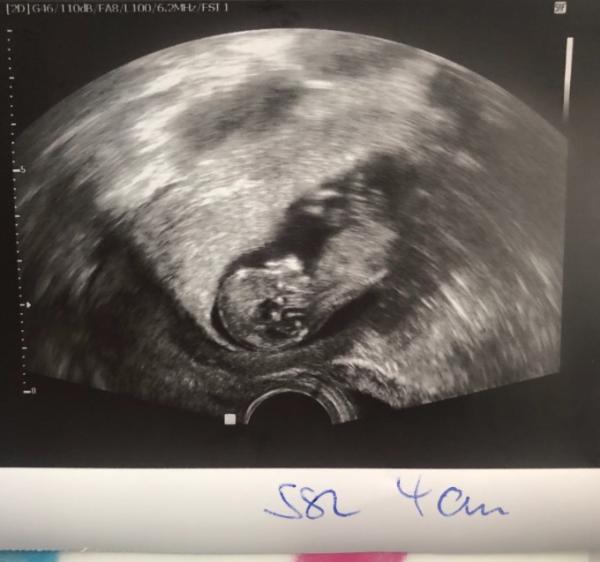

Hallo ihr lieben :) Bin heute 10+6 und hatte heute einen FA Termin, diese meinte zu mir das heute das letzte kostenlose US Bild gemacht wird.. mir ist bewusst dass die Krankenkasse leider nur 3 US Bilder übernimmt. Die FA hat eine sogenannte US Bilder Flatrate da soll ich einmalig 110€ bezahlen und jedes Mal bekomme ich dann ein US Bild. Wie ist das dann bei euch? Anbei noch das US Bild.. Würmchen war super fit und hat geturnt bis zum geht nicht mehr deshalb ist es auch nicht so ein schönes Bild geworden... da sind außerdem so viele Punkte am Kopf was ist das? Habe vor lauter Freude vergessen zu fragen Liebe Grüße Nini2503

Ein richtiger kleiner Mensch Wegen der Punkte mach dir bloß keine Gedanken. Ich weiß zwar nicht was das ist, aber dein FA hätte sicher was gesagt. Ich meine meine große hatte sowas auch auf den ersten Bildern.